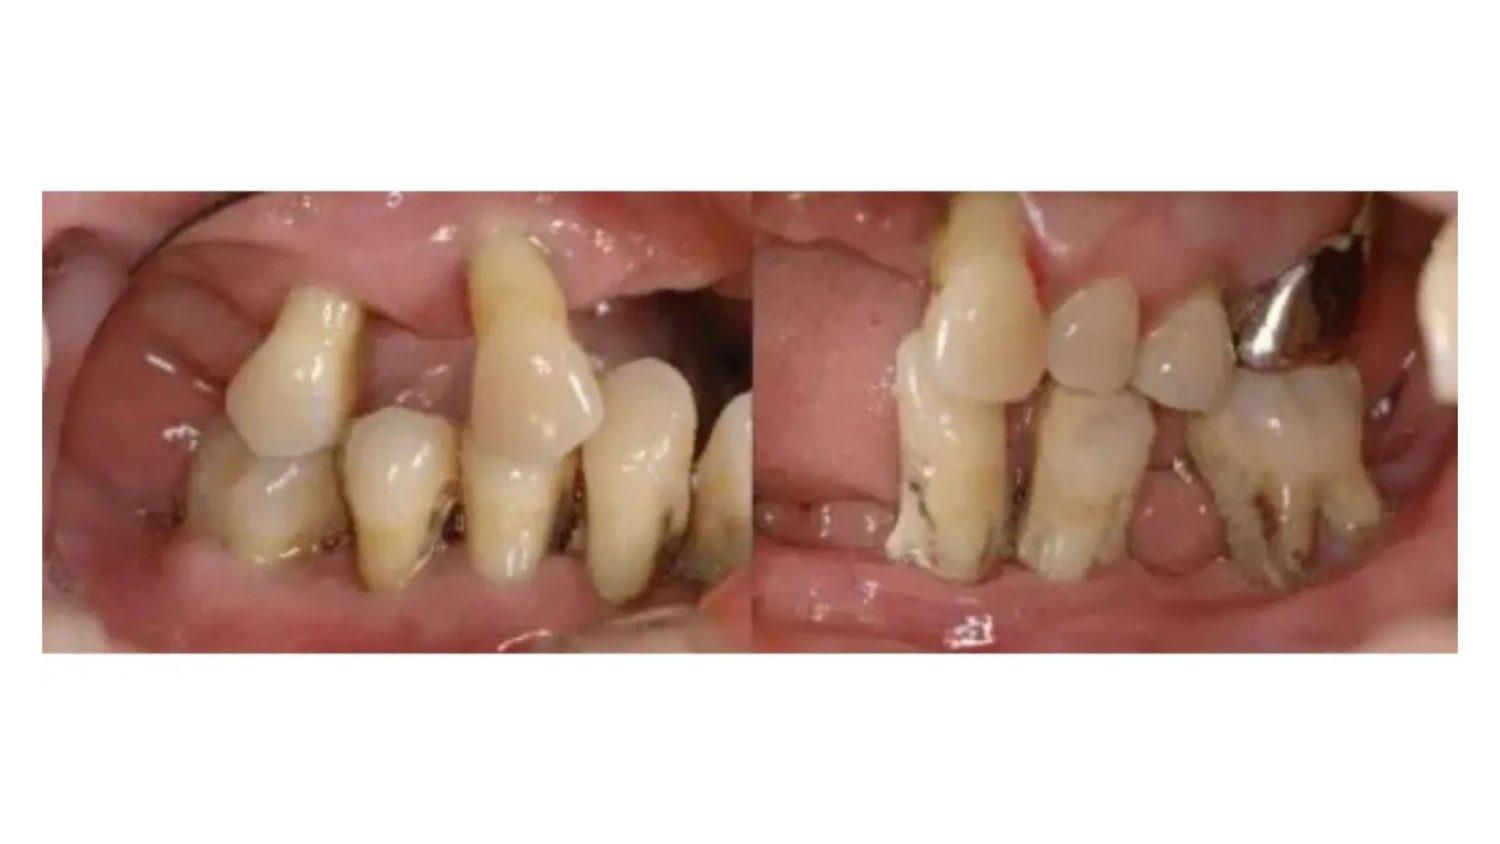

多数歯欠損のインプラント治療の症例(うえだ歯科)

| 主訴 | 歯がグラグラで噛むことができない。インプラントをして欲しい。 |

| 治療内容 | 歯周病で骨の吸収が重度で保存不能なため抜歯、仮の入れ歯を作り、6ヶ月の抜歯窩の治療の後に、インプラントのCTによる診査診断を行い、下顎に6本インプラント埋入と同時に仮歯を入れる。その後、上顎は8本のインプラント埋入と同時に仮歯を入れる。左右上6はソケットリフトによる上顎洞拳上術を行う。その後免荷期間6ヶ月待ってセラミックを用いた上部構造作製、装着しメンテナンスに移行する。 |

| 治療費 | 9,000,000円(税込) |

| 治療期間 | 2年3ヶ月 |

| 治療回数 | 90回 |

| 想定されたリスク | 重度の歯周病により無歯顎になったため、プラークコントロール不良による、術後のインプラント周囲炎が懸念される。歯冠の部分はセラミックなため欠ける可能性がある。 |